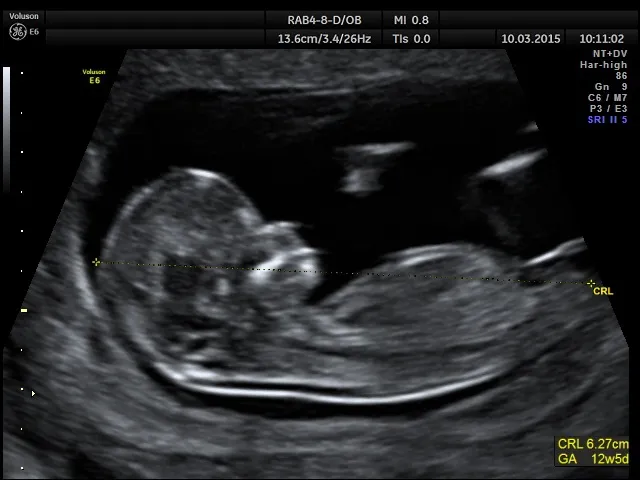

Co to jest pomiar CRL i dlaczego jest tak precyzyjny?

Kluczem do precyzji wczesnego USG jest pomiar długości ciemieniowo-siedzeniowej (CRL) zarodka. Jest to odległość od czubka głowy do końca tułowia dziecka. W pierwszym trymestrze, kiedy zarodek jest jeszcze mały, jego wzrost jest bardzo przewidywalny. Dzięki temu, na podstawie pomiaru CRL, lekarz jest w stanie z dużą dokładnością określić wiek ciąży.

Badanie USG wykonane w pierwszym trymestrze ciąży, najlepiej między 7. a 12.-13. tygodniem, jest uznawane za najdokładniejszą metodę określania wieku ciąży. W tym okresie rozwój zarodka jest bardzo dynamiczny i jednolity u wszystkich kobiet, co pozwala na precyzyjne pomiary i ustalenie terminu porodu z marginesem błędu wynoszącym zaledwie kilka dni.